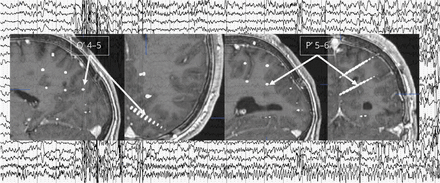

封面图片:同时头皮脑电图和SEEG左parieto-occipital沟发作的录音。程式化的凯特林阿曼•兰姆、高级数字多媒体/图形协调员。看到页面e2045